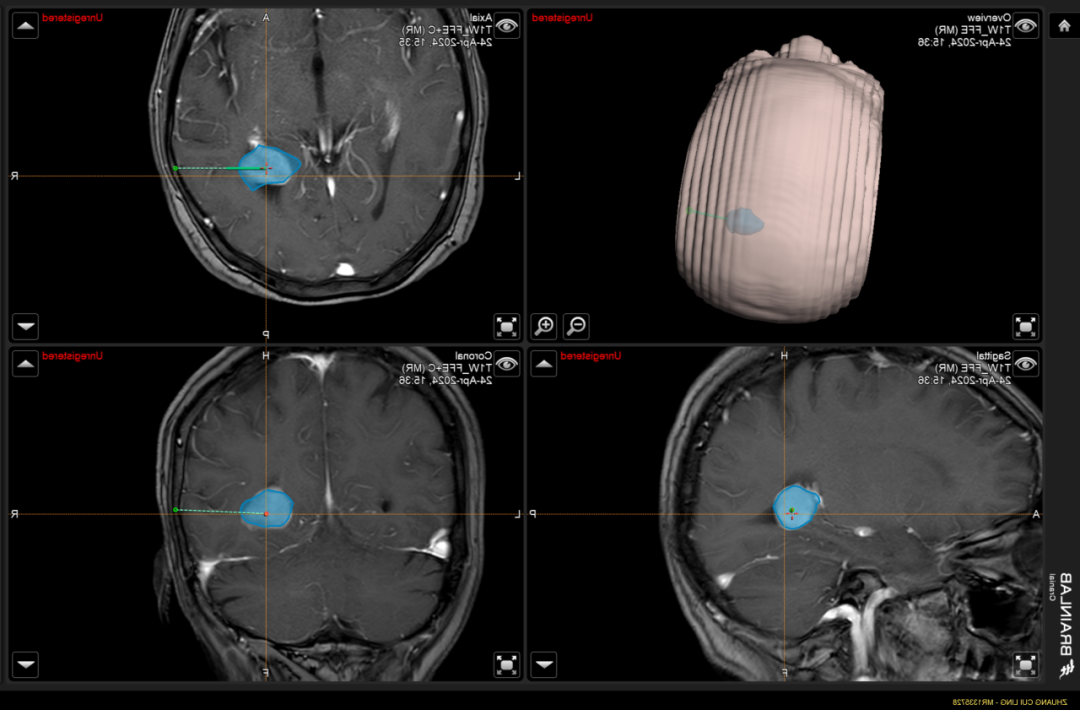

▲患者头颅MR增强

考虑脑膜瘤可能!

入院后,神经外科主任王文华立刻组织术前讨论并表示:该患者肿瘤位于三角区,位置较深,肿瘤大小2.2cm*1.6cm,肿瘤周围血管、神经丰富,手术难度较大,传统开颅肿瘤切除术中出血多,肿瘤定位困难,对血管神经的破坏较大。市中医医院引进的术中导航系统可以精准定位肿瘤,计算最优路径,减少脑组织的损伤,减少术中出血。

▲术中神经导航模拟肿瘤位置,精准定位,计算最优路径

经神经导航的辅助,选取微创小切口,完整切除肿瘤,术中出血少,对功能区保护满意。